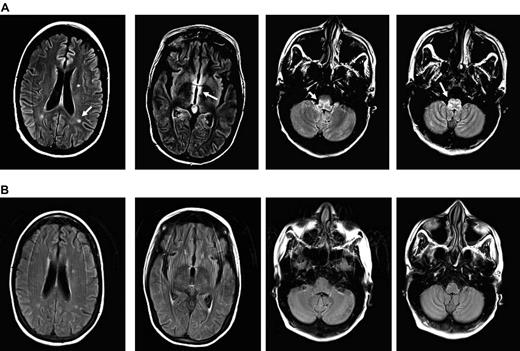

MRI images of CMV encephalitis before and after U-DLI. (A) Axial T2 fluid-attenuated inversion recovery (FLAIR) images demonstrate 3 new white matter lesions, increased signal, and edema in the periventricular region most notable around the third ventricle and medulla (white arrows). (B) Axial FLAIR images demonstrate resolution of previously described lesions and increased signal/edema 6 months after the initial U-DLI.

We recently treated a 29-year-old woman with R-CMV encephalitis with 5 sequential donor lymphocyte infusions at escalating doses using her backup U-DLI/stem cell products. The patient had received an A antigen-mismatch unrelated allogeneic peripheral blood stem cell transplant after myeloablative conditioning with total-body irradiation and melphalan for multiply relapsed γ-δ T-cell lymphoma. Both the patient and her donor were CMV antibody–reactive before transplantation. GVHD prophylaxis included tacrolimus, methotrexate, and antithymocyte globulin. She engrafted on day +18 and developed a presumed gut GVHD requiring a 2-week course of systemic corticosteroid. CMV reactivation, measured in plasma, was first noted by PCR on day +7 (2951 copies/mL) when she had also pneumonitis. She spent most of her posttransplantation period in the hospital because of persistent CMV viremia and recurrent bacteremia. Her viremia was never controlled despite prolonged courses of ganciclovir or foscarnet treatments. There was also no evidence of sustained CD4/CD8 recovery despite discontinuation of immunosuppression. Her lymphoma remained in remission with 100% donor myeloid and lymphoid chimerism by bone marrow and peripheral blood short-tandem repeat analyses. On day +107, she developed increasing somnolence, disorientation, nystagmus on a right gaze, and profound weakness. The diagnosis of CMV encephalitis was made based on MRI of the head, which showed restricted diffusion areas and round lesions within the periventricular white matter, medial left temporal lobe, and medulla with associated enhancement (Figure 1A), and high titers (388 660 copies/mL) of CMV detected in her cerebrospinal fluid (CSF) by quantitative PCR. CSF sample showed WBC of 2, RBC 0, normal glucose, and slightly elevated protein. Cytology revealed a few lymphocytes and monocytes. Simultaneous blood CMV viral load was 49 680 copies/mL. It was later found that the CMV was ganciclovir-resistant because of UL97 L595W mutation, detected in a blood sample. UL54 mutation was also tested by PCR but the result was inconclusive because of technical reasons. The patient also received leflunomide, cidofovir, IVIG, and CMV-specific IVIG at different time points for persistent CMV with producing marginal benefit, if any.

The patient's neurologic status and T-cell counts remained unchanged despite a decline in CMV copy number after the initial U-DLI, which was given on day +112 (Figure 2). She was 100% donor T-cell chimera before DLI. Following the third U-DLI, she developed localized chronic skin and ocular GVHD, which responded to topical treatments. This was associated with temporary increase in peripheral blood CD4/CD8 counts. After the fourth U-DLI, given at higher doses, her CD4/CD8 counts further increased and remained high afterward. This was clearly associated with decrease in her CMV viral load by PCR (Figure 2) and CMV antigenemia. No steroid therapy was given during any of the DLIs. Antiviral therapy was discontinued because of lack of clinical efficacy. Her neurologic recovery, however, lagged behind viral clearance following U-DLIs. She developed biopsy-proven grade 2 skin GVHD after the last (fifth) high-dose DLI, which responded to a short course of a systemic steroid. Most recently, her CMV was undetectable or positive at very low titer with relatively high peripheral T-cell counts. Her neurologic condition improved in parallel with resolution of MRI lesions (Figure 1B). A follow-up CSF sample examination on day +357 was negative for CMV by PCR.